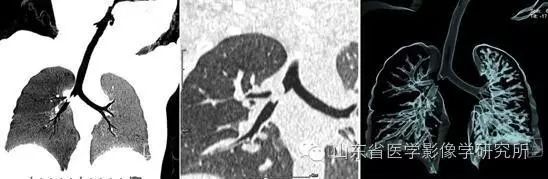

▲ 1岁小孩吃了八宝粥后出现咳嗽、气喘的症状。 低剂量胸部CT扫描+大气道重建后,利用MinIP和VR技术可以清晰显示右主支气管内的异物。